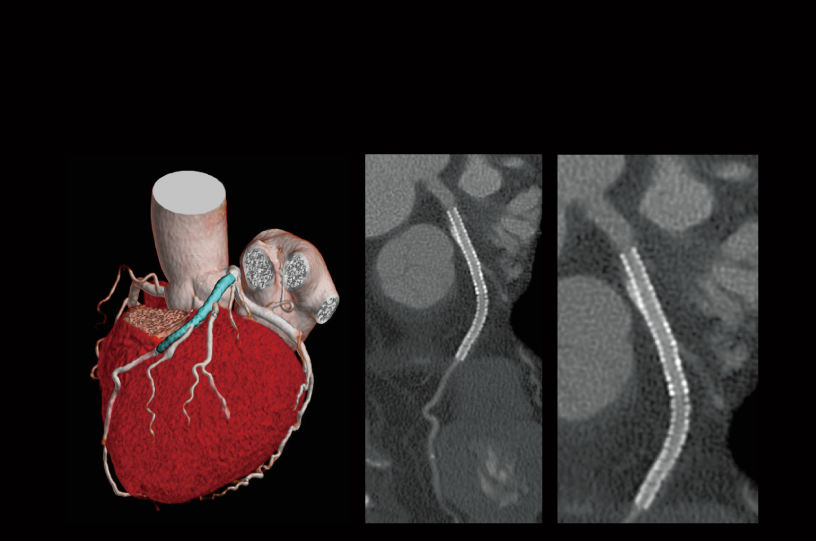

Coronary artery calcification

Follow-up after CABG

Follow-up after LAD stenting